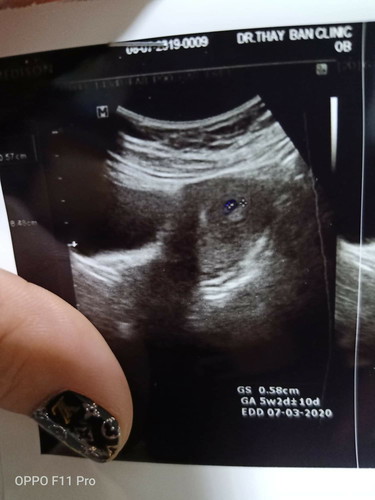

หมอบอกแต่มีถุงน้ำคร่ำอยู่แต่ยังไม่เห็นตัวเด็กเพราะเล็กมาก ประมาณ5มิลค่ะปกติไหมค่ะคุนแม่ท่านไหนเป็นแบบแม่บ้านนี้บ้าง

เพิ่ง5วีค ยังไม่เห็นนะคะ แต่เจอถุงแล้วก้อเป็นสัณญานที่ดีค่ะว่าไม่ท้องนอกมดลูก รอหมอนัดครั้งหน้านะคะ ให้เวลาน้องโตค่ะ .

5วีคเจอถุงน้ำเหมือนกันคะ หมอนัดอีกที7วีคเจอหัวใจกระพริบๆเล็กๆ ดีใจมากคะ ก่อนหน้านี้เคยท้องลม